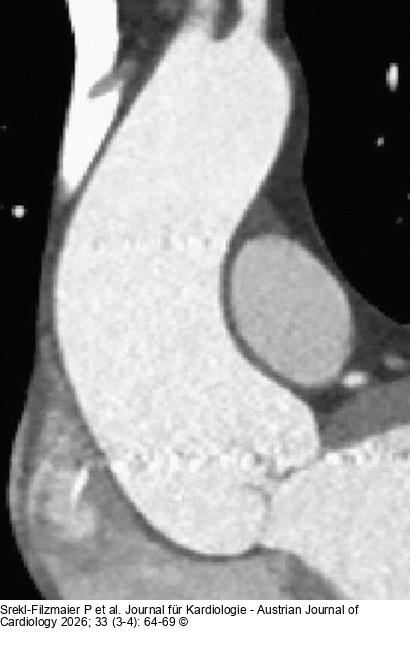

Abbildung 1: Phänotyp Abbildung 1: Wurzel-Typ |